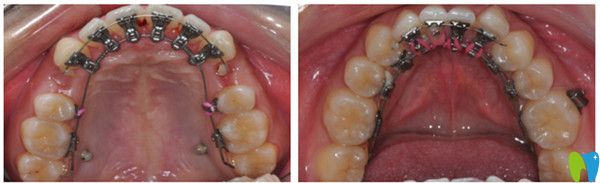

舌側(cè)隱形矯正前后療效圖